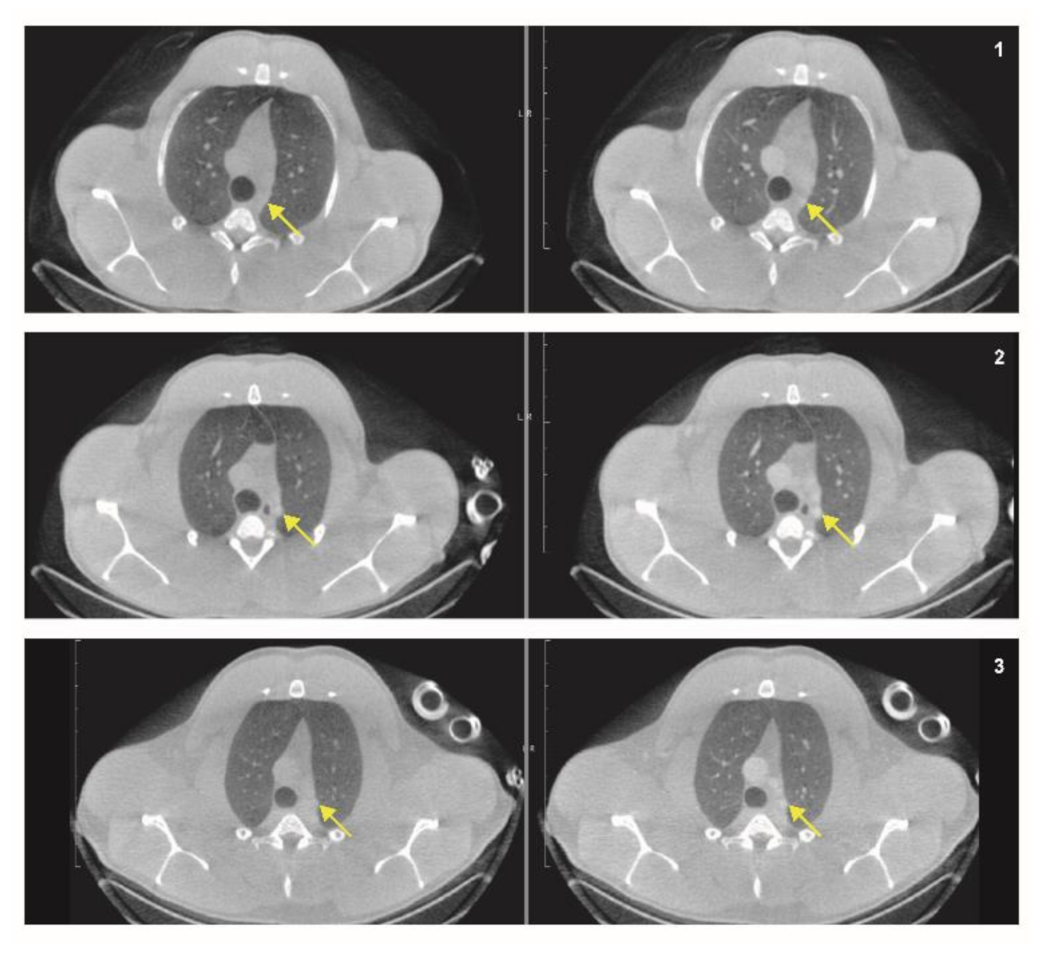

3.2.1. CT

3.3.2. Attenuation Correction